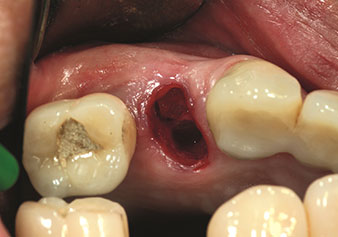

Piezo cerrahisi ile ekstraksiyondan sonra durum

Şekil 2: Piezo cerrahisi ile ekstraksiyondan sonra durum. Fotoğraf: © Dr Torsten Conrad (Bingen am Rhein)

Bu, daha sonra veya hemen implant bakımı için optimum bir temel oluşturur [şekil 1 ve 2, Dr. Torsten Conrad’ın (Bingen a. Rhein) onayı ile kullanılmıştır].